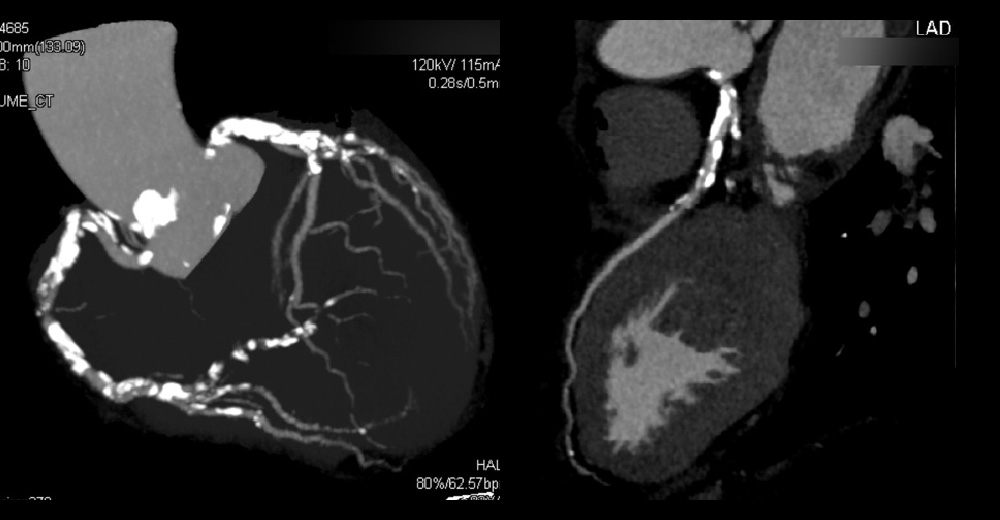

3. 造影心臓CT

進行期 単純CT 重症心筋虚血症例

進行期 造影心臓CT 重症心筋虚血症例